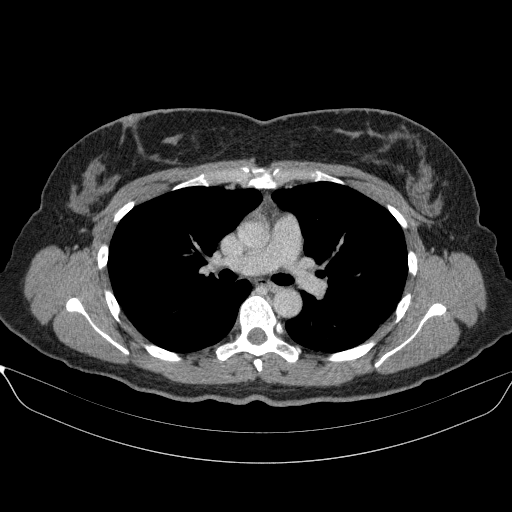

Reconstructed NATIVE CT scan (cycle consistency)

Full window (WL 1023.5, WW 4095 β†’ Low βˆ’1024, High +3071)

Lung window (WL -600, WW 1500 β†’ Low βˆ’1350, High +150)

Mediastinum window (WL 40, WW 400 β†’ Low βˆ’160, High +240)